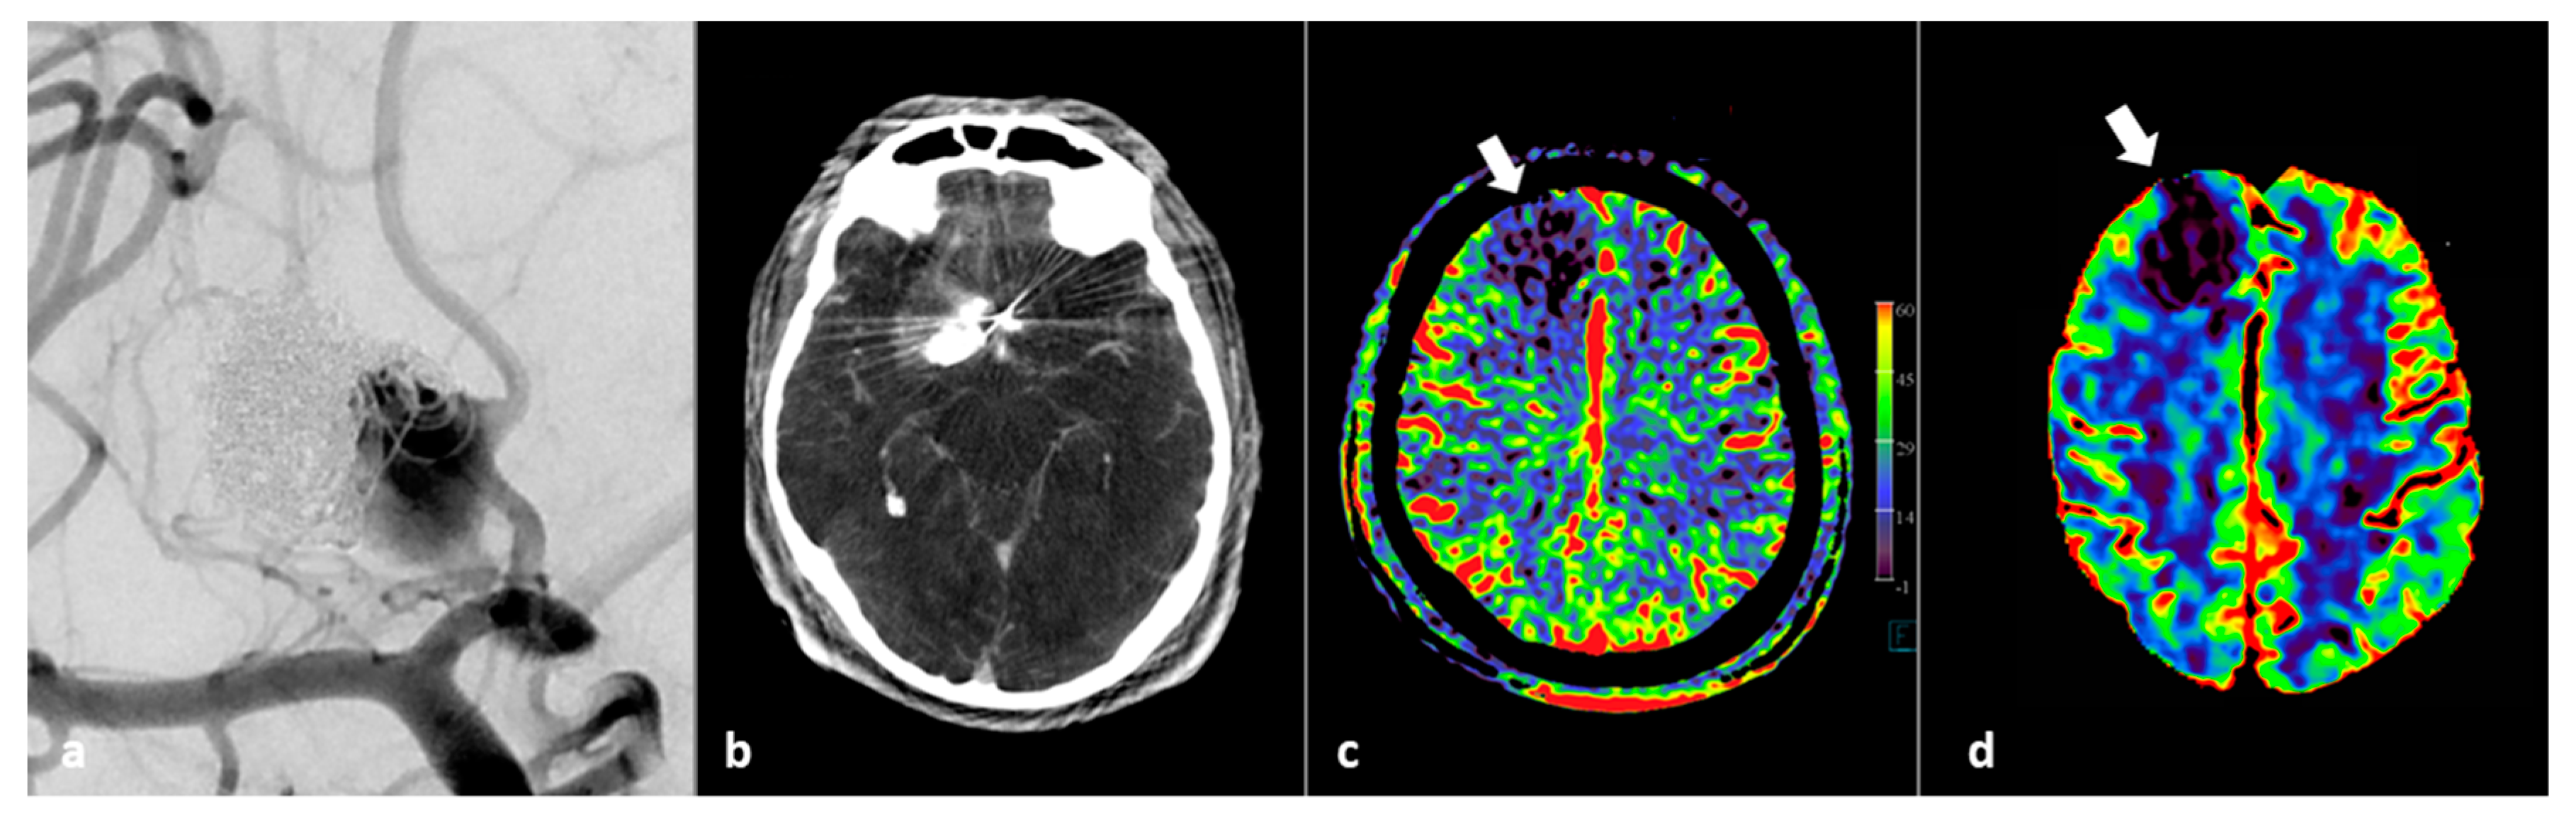

Figure 6 illustrates the use of FD CT imaging for monitoring of occurrence of an endovascular complication.

Figure 6.

FD CT PBV imaging in a 46-year-old patient with thrombo-embolic and hemorrhagic complications during flow diverter placement. (a) AP view DSA image pre-intervention shows a significant neck remnant after previously coiled pericallosal aneurysm. (b) FD CT axial MIP reformation after occurrence of complications shows local hematoma and contrast. (c) Post PVO FD CT imaging shows right frontal residual wedge shaped perfusion deficit (white arrow). (d) Follow-up conventional MD CT CBV perfusion confirms local perfusion deficit.